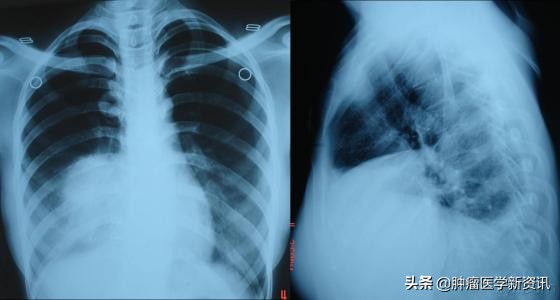

通过下面的患者CT图,我们可以看到肿瘤逐渐的消失,接受4次NK免疫细胞疗法+抗癌剂后,患者原发肿瘤几乎完全消失了。目前该患者身体状况也得到了明显改善,不仅胸痛消失了,食欲也恢复了,身体活动也变得灵活了,咳嗽和痰出血的现象也消失了。